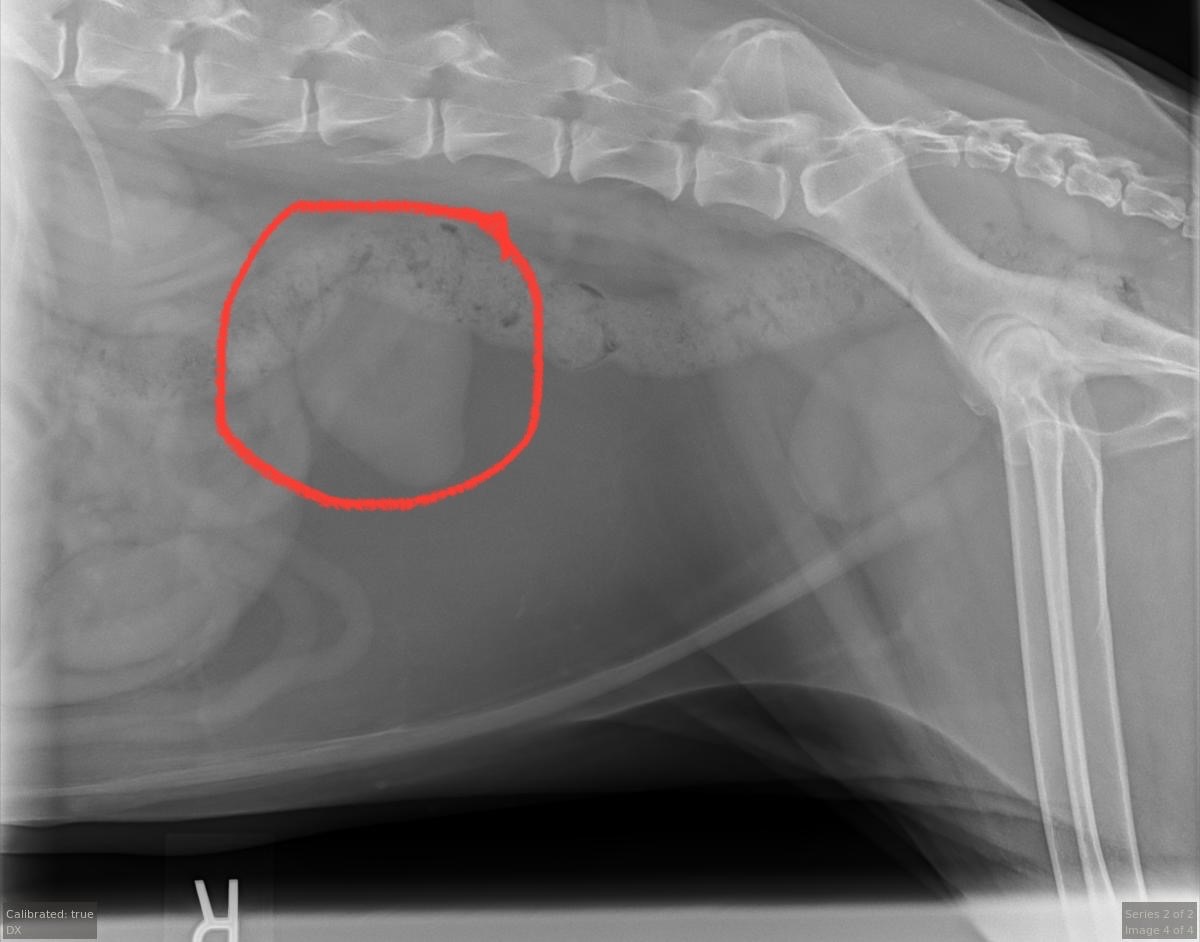

As some of you know, my dog (AKA the love of my life) was recently diagnosed with a large internal tumor. It was initially thought to be a pheochromocytoma, which is a very rare type of adrenal tumor that not much is known about. A soft tissue veterinary surgeon recently reviewed the imaging and expressed doubt about this diagnosis, and believes it is some kind of abdominal tumor. She is conferring with the veterinary cardiologist who issued the first diagnosis as well as Nalu’s main vet to come to a cooperative conclusion and plan our next steps. Whatever it is, it is growing quickly, and will become fatal if it is not removed.

Given that we can address the source of her arrhythmia (which was the catalyst for diagnostic imaging that led to the discovery of the mass), the prognosis is good! Her blood work is normal and she is a healthy 11-year old dog otherwise, and I am not ready to give up on her.

Surgery is expensive, but allowing this tumor to progress would diminish her quality of life, and it’s much too soon to consider euthanasia, considering she is showing little to no symptoms of other health issues. Surgery would prolong our time together. Nalu is loved by so many and we appreciate any and all help and support!